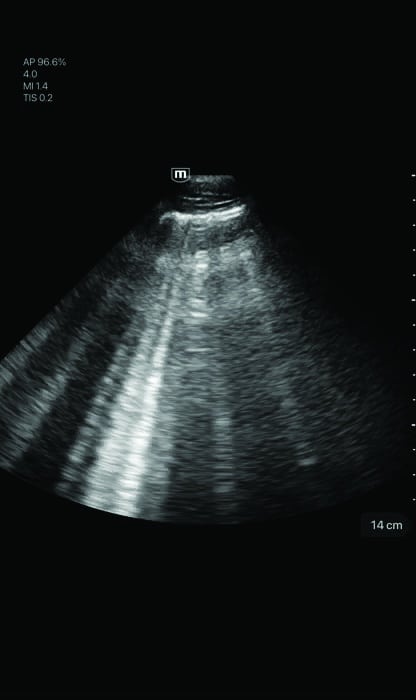

- Scanning modes: B-mode, M-mode, Color Doppler, Power Doppler, PW, and Tissue Doppler Imaging

- Dedicated presets for Cardiac, Abdomen, Lung, Transcranial Imaging (TCI), Emergency Medicine (EM), Trauma (FAST), EM Abdominal

- Aortic Aneurysm (AAA), Bladder, OB/GYN, and Vascular

Clinical Images